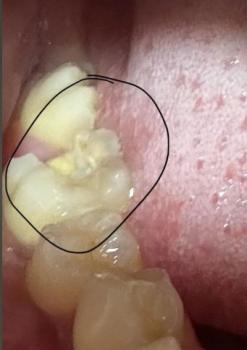

This image shows a patient wearing fixed orthodontic braces on the lower teeth with red elastic ligatures and a visible archwire. The upper teeth are not braced in this image. The lower gum tissue appears mildly irritated in areas where brackets and wire contact the soft tissue, which is common during active orthodontic treatment.

Lower anterior and posterior teeth fitted with brackets and archwire

Upper teeth visible without braces

No obvious tooth fractures or active decay visible

Primary concern relates to orthodontic forces and soft-tissue response

Orthodontic brackets bonded to lower teeth

Red elastic ligatures indicating active adjustment phase

Mild gum redness near bracket margins

Teeth in active alignment and leveling stage

No signs of abscess or acute infection